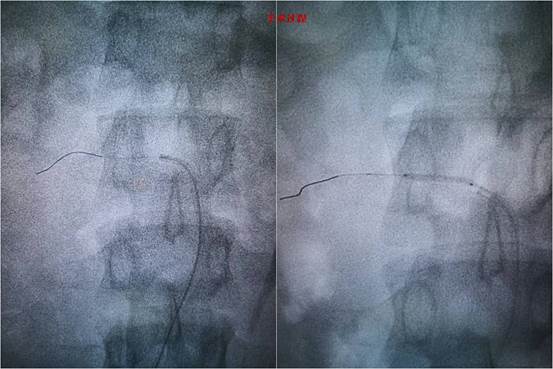

图-2 手术过程

患者,未成年男性,在当地因高血压病就诊检查,发现可能存在肾动脉狭窄可能,患者血压最高达200/146mmHg,为进一步诊治慕名来到交大一附院血管外科杨林教授门诊。患者入院后,在科室禄韶英主任指导下,杨林教授及诊疗团队韩阳医师,武士琪医师,李小兵医师对其进行了完善的术前检查、术前准备及药物治疗。进一步明确患者为肾动脉闭塞,手术难度极大,手术风险极高。考虑到患者未成年,为保留患者潜在的肾功能,同时避免采用常规的金属支架技术。杨林教授团队经过详细的术前讨论后和设计手术方案后,决定给患者实施局麻微创的药物球囊成型技术。在介入手术室的配合下,发现患者为右肾动脉闭塞,远端通过毛细血管代偿,手术团队通过精细的微创技术,反复尝试都未能通过闭塞段血管,最后通过各种微导丝、微导管技术的联合应用终于通过闭塞的肾动脉,然后通过小球囊预扩张,过渡到常规球囊扩张,最后为患者实施药物球囊扩张成形术,患者闭塞的肾动脉得到完美重建。患者术后在血管外科医护团队的严密监控下顺利恢复。术后血压即恢复正常,于近日顺利出院。